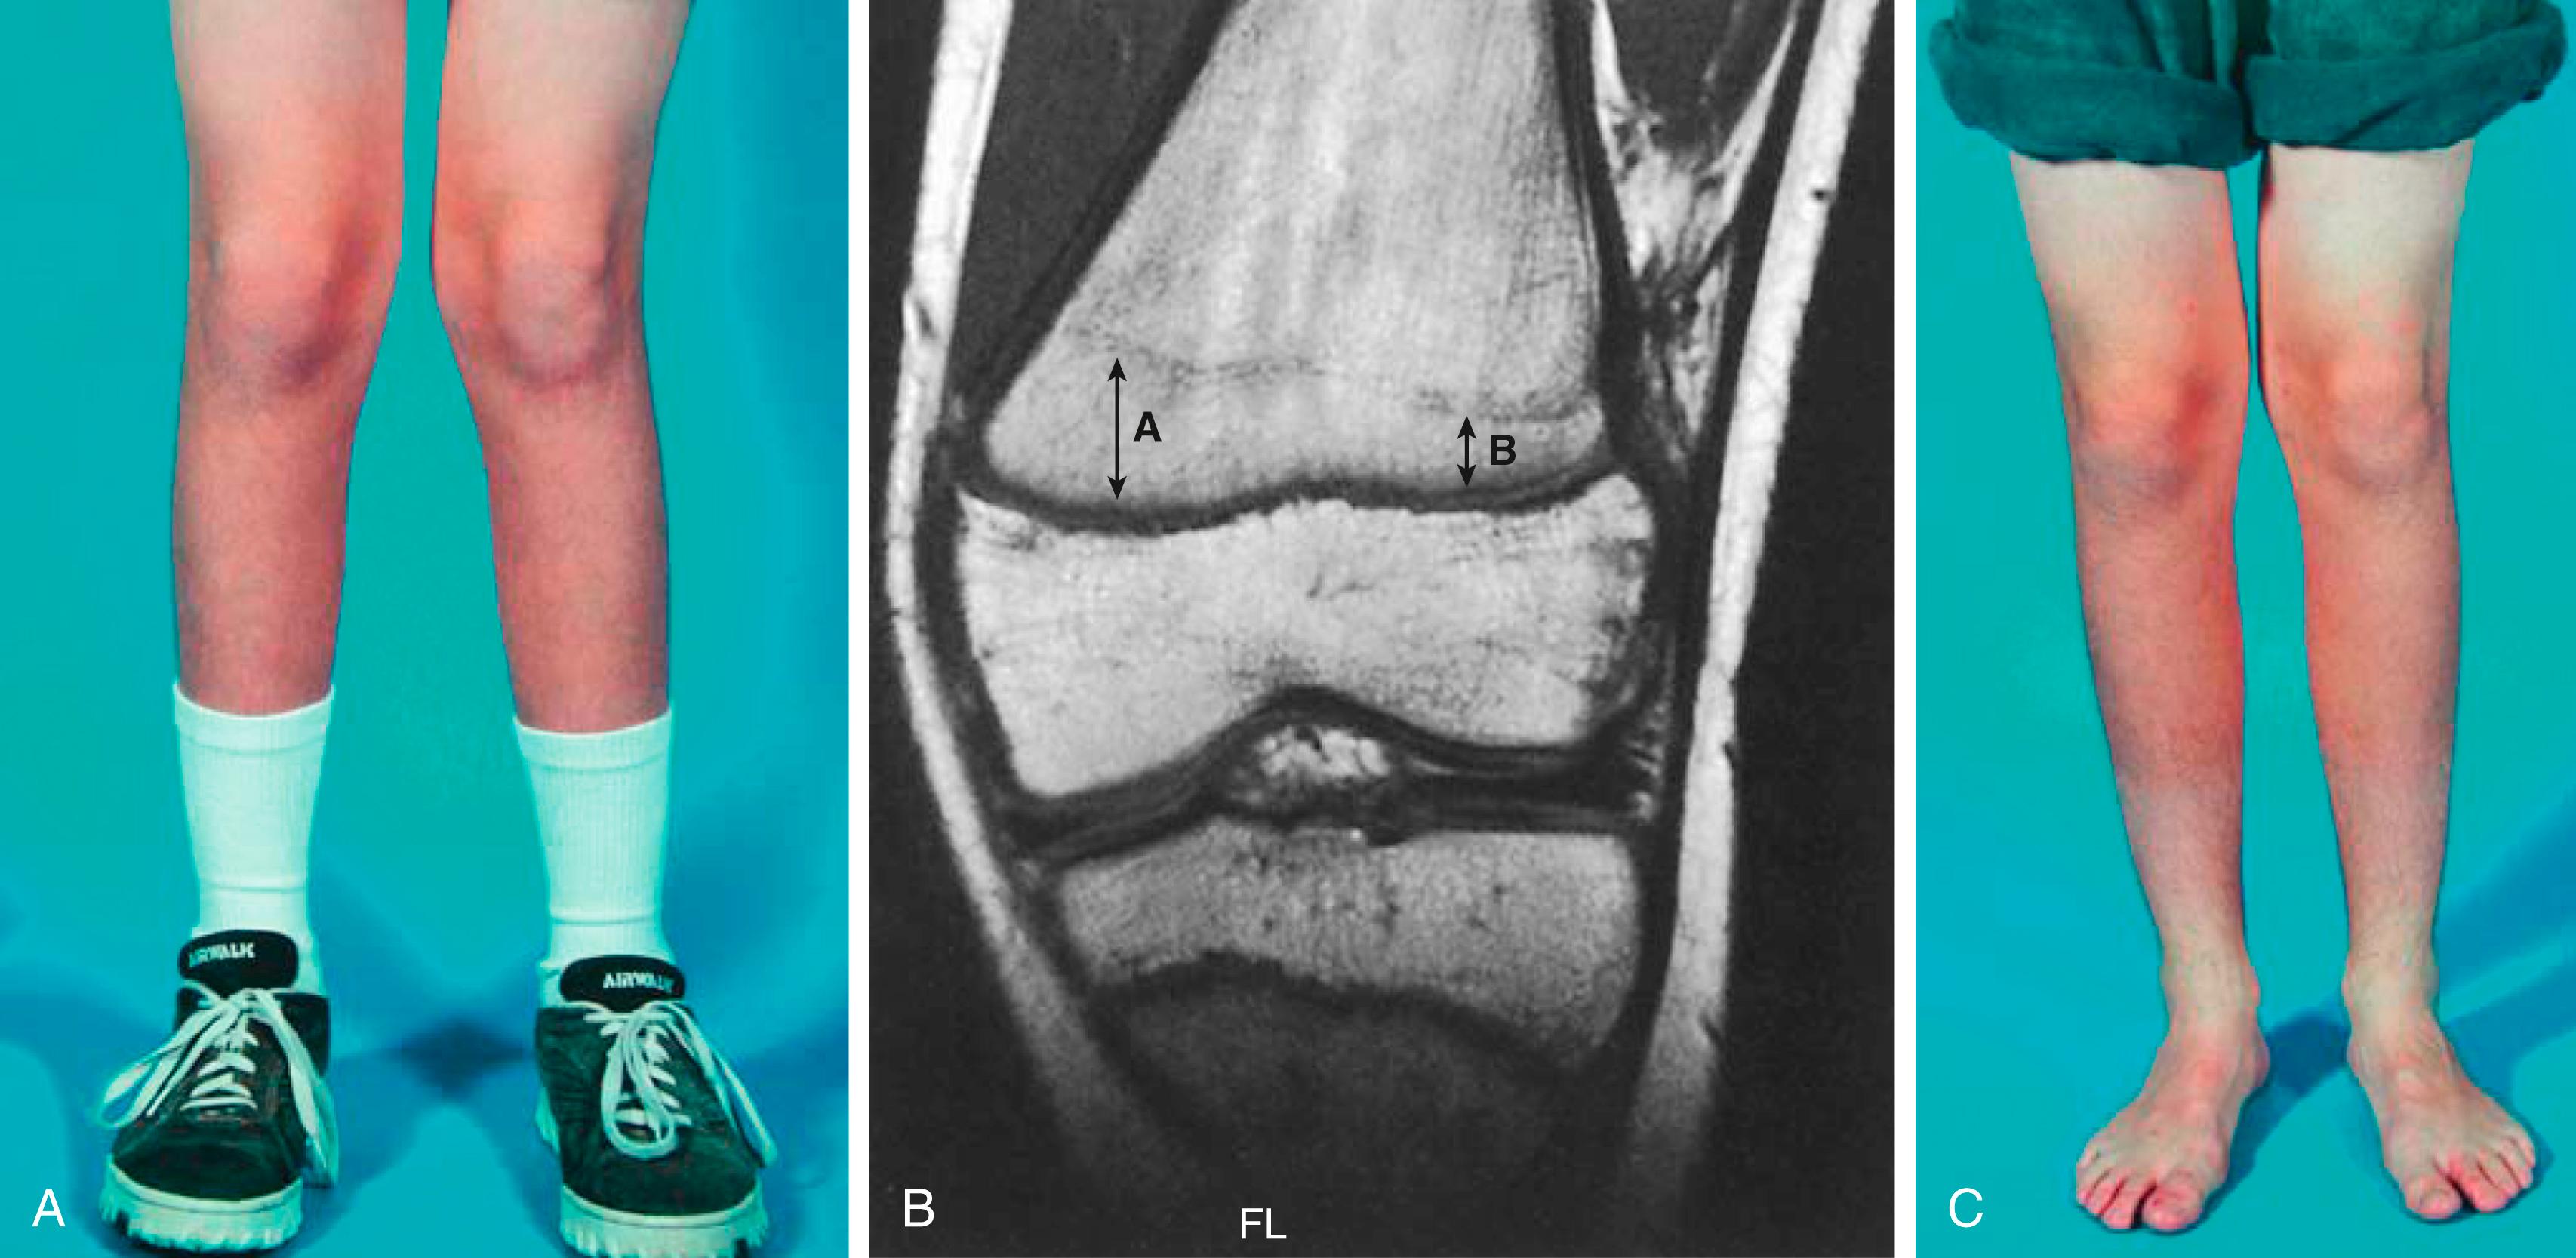

Fig. 27.12, Asymmetric growth following a Salter-Harris type II distal femoral fracture. (A) Valgus deformity 15 months after fracture. (B) Magnetic resonance image demonstrating asymmetric growth of the distal femoral physis. The distance from the physis to the Harris growth arrest line is greater medially (A) than laterally (B). The fact that the growth arrest line has migrated proximally on the lateral aspect reflects a slowing of growth rather than a complete arrest. (C) Clinical appearance 8 months after a medial distal femoral epiphysiodesis was performed. Lateral growth continued until the deformity was corrected. At this point, a lateral hemiepiphysiodesis and a contralateral epiphysiodesis were performed. An 8-plate procedure would have also been appropriate for this case.